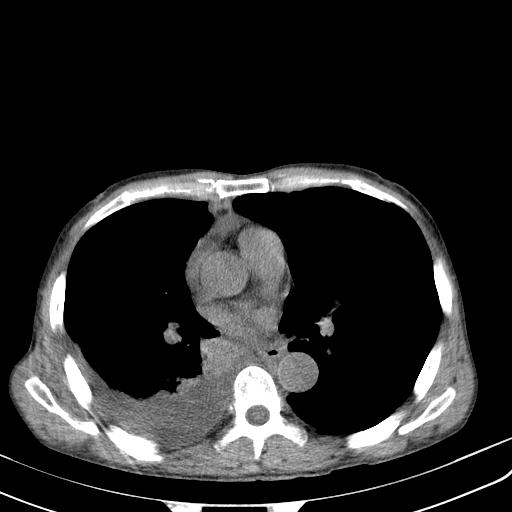

男性 75  咳嗽 一周前发热最高达39

结核的基础上有纵隔淋巴结肿大,右侧有胸水,但右侧纵隔反而窄,说明有肺有不张。

再就是右下肺有块影,和不张混合,还是不能除外肺癌。

补充材料,患者2月份ct片大致正常,双侧胸腔积液,2月份抽胸水未发现ca细胞,现患者发热,痰多,各气管通畅,

1)右肺继发型肺结核。2)左肺胸膜下多发性肺大泡。3)右侧胸腔积液。